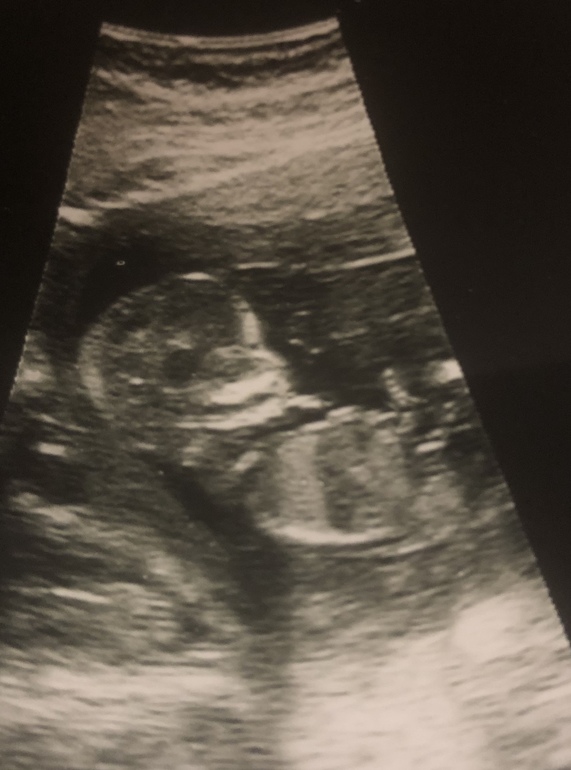

Наконец-то первый скрининг !)

Девочки, все ли нормально?

Носовая косточка не короткая?

Все нормально, главное чтобы носовая кость визуализировалась, во многих местах вообще не пишут её длину.. По фото нельзя даже предположить пол, потому что бугорка не видно.. А вообще это не совсем достоверный метод определения, у нас был бугорок вверх, но я беременна девочкой. Кстати даже в 16 недель ошиблись с полом.. Сказали 98 % мальчик, а в 18 недель на плановом узи уже девочка) Поэтому чем позже будет определён пол, тем лучше, т.е. намного достовернее на втором скрининге.

По-моему, все у вас хорошо. Моим вообще не меряли носовую кость, просто написали "визуализируется".